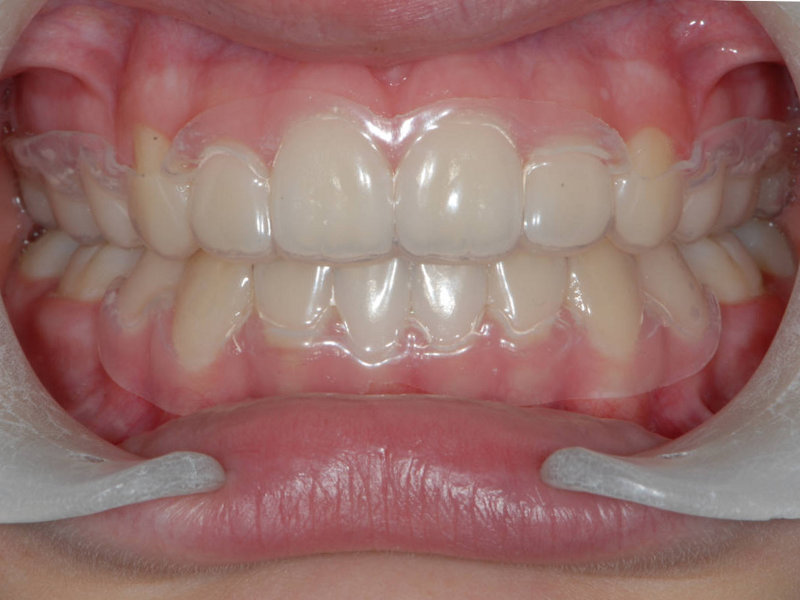

Essixskena (C)